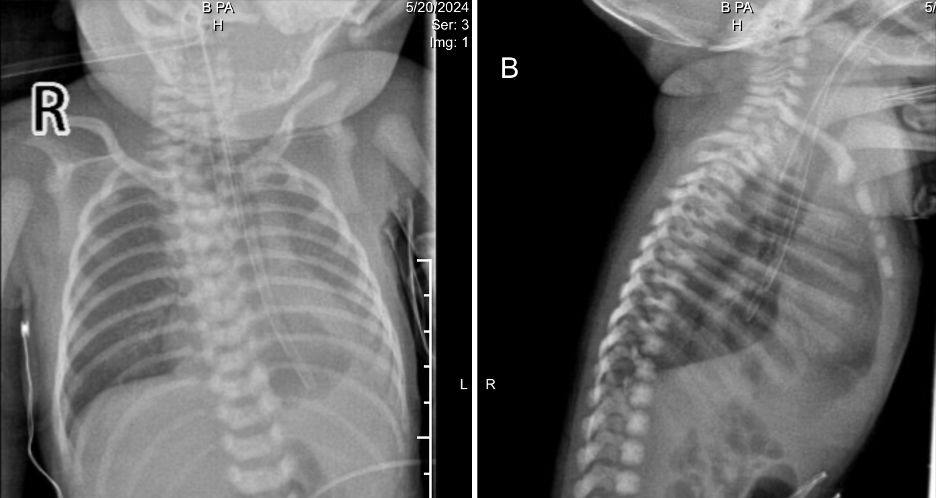

Ventilator air leak prompted re-intubation with a size 3.5 tube. Videolaryngoscopy revealed a slit-like laryngeal deformity (Figure 1.). Bedside echocardiography reaffirmed DORV with pulmonary stenosis. Initial chest radiography (Figure 2.) showed a left lower lobe opacity and a feeding tube in the distal esophagus. The initial impression included neonatal pneumonia with polymalformative features: possible laryngeal cleft, double outlet right ventricle (DORV), esophageal atresia (EA), and tracheoesophageal fistula (TEF). Upon admission, empiric IV antibiotics were started. Referrals to Pediatric Cardiology for evaluation of DORV and to Pediatric Surgery for assessment of suspected EA/TEF were made. A Pediatric Pulmonology consult was eventually obtained for airway assessment due to consideration of laryngotreacheoesophageal cleft.

AP and lateral chest X-rays after intubation

Figure 2. AP and lateral chest radiographs post-intubation showing homogeneous opacity at the left lower lobe obscuring the left hemidiaphragm and sulcus.